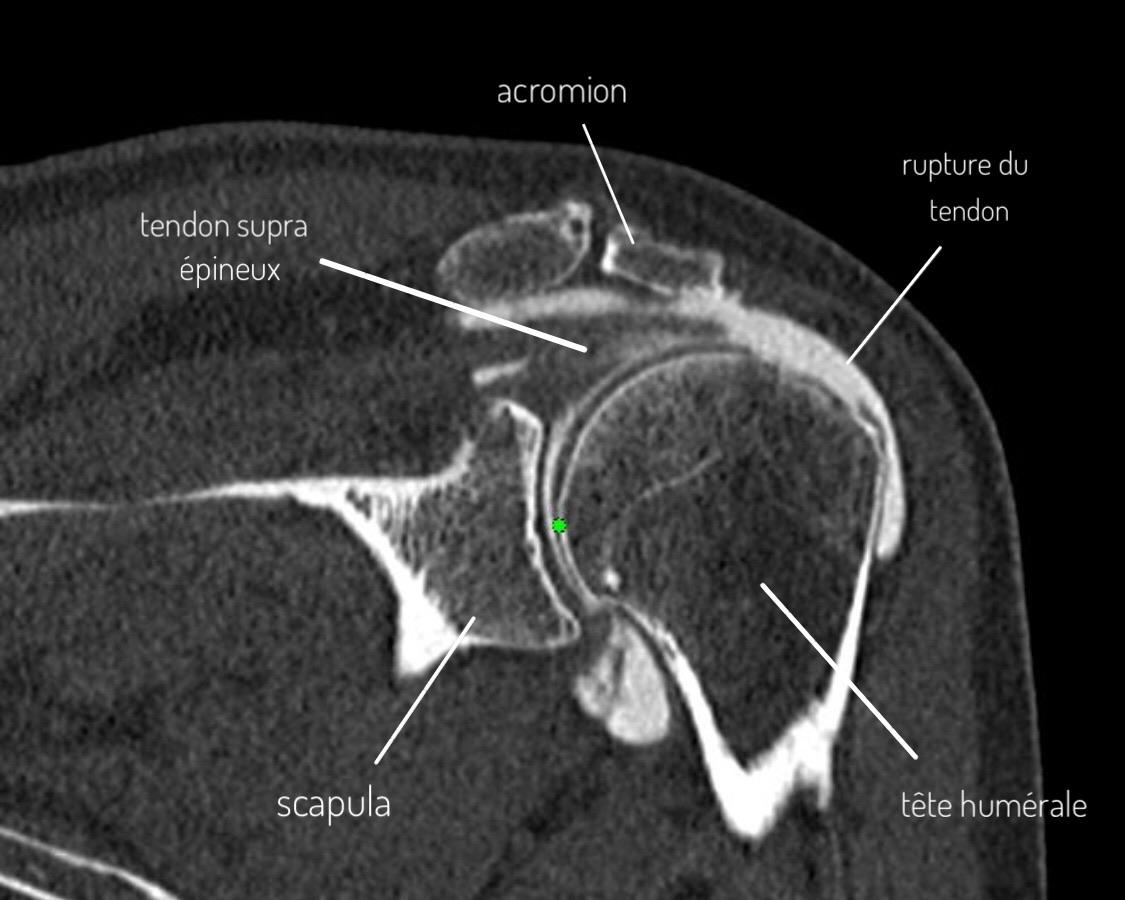

Arthro-CT montrant une rupture du tendon supra-épineux consécutive au conflit sous-acromial

Arthro-CT : Rupture du tendon supra-épineux (conséquence du conflit sous-acromial)

L'arthro-IRM ou l'arthroscanner : examen de référence

Au cours de cet examen, on réalise une injection de produit de contraste dans l'articulation de l'épaule (entre la tête de l'humérus et l'omoplate), suivi d'un scanner ou d'une IRM.

La répartition du produit de contraste dans l'articulation va permettre une parfaite visualisation des différents tendons de la coiffe des rotateurs ainsi que des structures osseuses, cartilagineuses et ligamentaires.

Cet examen va donc permettre de visualiser des éventuelles fissure ou rupture complète ou incomplète de la coiffe des rotateurs, conséquence du conflit sous-acromial prolongé.